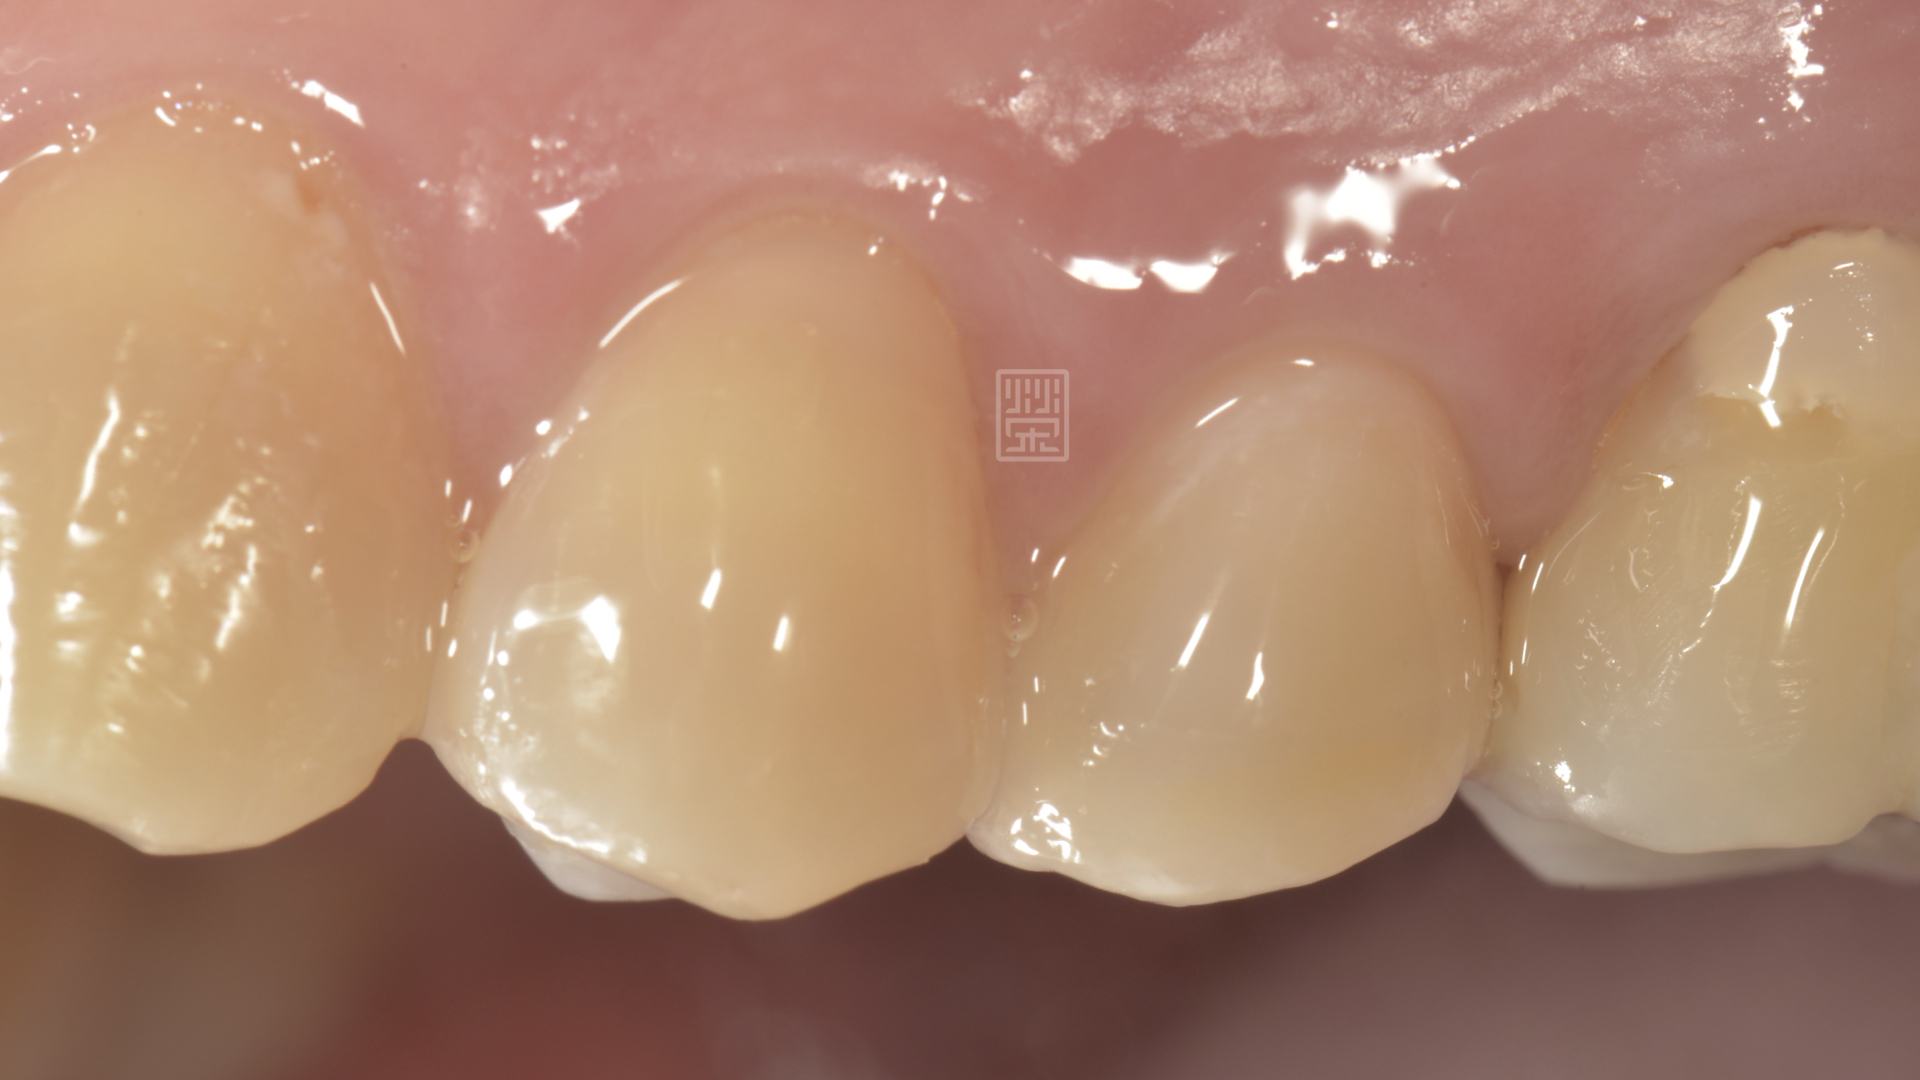

陳先生覺得牙齒有的地方咬起來怪怪的,口內檢查看到牙齒有個裂痕。

牙齒旁邊有裂痕